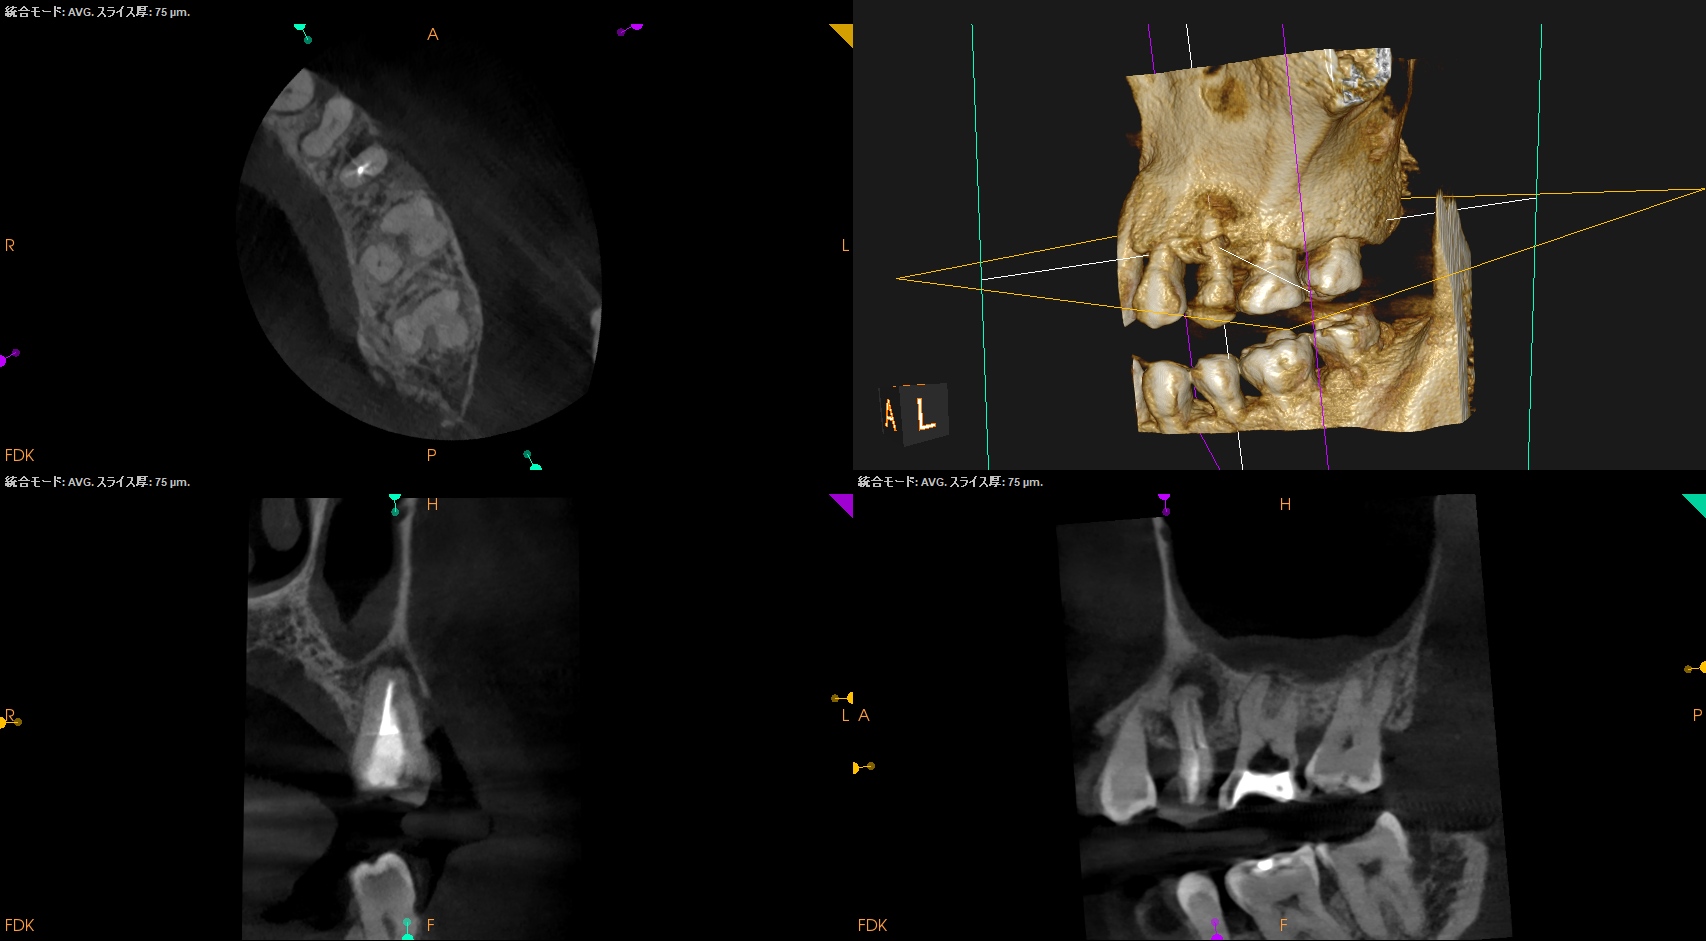

CBCTも撮影した。

これはマストの医療行為である、と私からは告げておこう。

#14

MB

MB2

DB

P

B

おおよその作業長が類推できる。

が、いずれにしてもこの治療での最大のポイントになるのはMB2がどこにあるか?である。

MB2の根尖部にはCBCTで根尖病変があるからだ。

作業長が術前に予測したCBCTでの作業長に近似していること

を。

これが、

CBCTの威力

である。